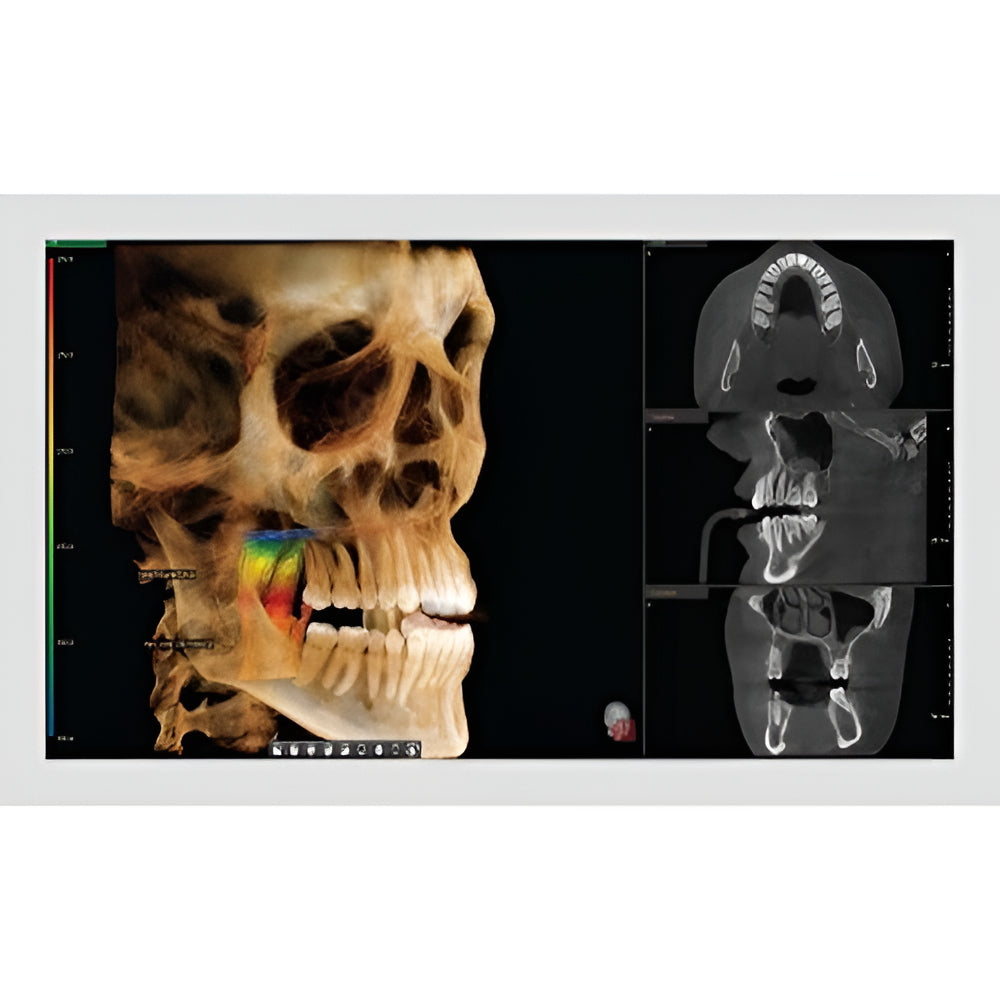

The Vatech PaX-i3D Green panoramic plus cone beam system delivers large field of view (up to 15 x 15 cm) dental CBCT scans in addition to standard 2D panorex and extraoral bitewing X-ray images. This Vatech CBCT machine features the innovative green CT technology which minimizes patient dose, while the Rapid Scan feature delivers high-quality 3D cone beam scans in just 5.9 seconds. A quick exposure time helps to minimize artifacts and motion, while at the same time reducing patient dose, making your imaging process more efficient and safer.

- EZ3Di Imaging Software with License

- 3D Cone Beam

- Large FOV

- Multi-FOV

- Focused FOV